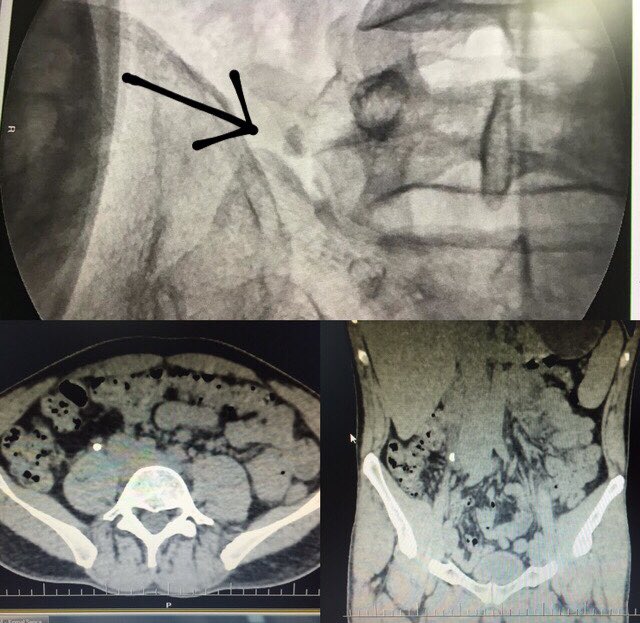

Introducing STONE PASS A community education effort to improve ureteral stone discussions between patient & provider A tool to communicate probability based on outcomes of similar patients (size, location, & #PROMIS pain) It's all about decision making stonepassapp.com